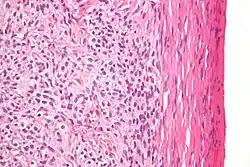

| High magnification micrograph of a thecoma. H&E stain. | |

Pathologic features

Grossly, the tumour is solid and yellow.

Grossly and microscopically, it consists of the ovarian cortex.

Microscopically, the tumour cells have abundant lipid-filled cytoplasm.